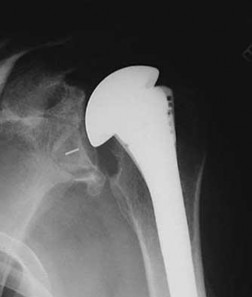

What is the most likely explanation for the change between the initial intraoperative radiograph (Figure 11a) and the radiograph taken 4 weeks after surgery (Figure 11b) in an 87-year-old man who underwent primary hip replacement for osteoarthritis?

The image demonstrates subsidence of the femoral implant. The implant subsided because it did not have good initial stability. The tapered femoral implant was placed after initial preparation for an anatomic femoral stem. A limited, nondisplaced femoral neck fracture was encountered during the procedure and treated. Two advantages of tapered stems are the efficient transfer of stress to the proximal femur and the ability to accommodate some subsidence to achieve enhanced stability. Although subsidence of a tapered stem to a more stable position can produce a good result, quality of metaphyseal bone should be considered. Attention to surgical technique remains important to optimize component stability for biological fixation.